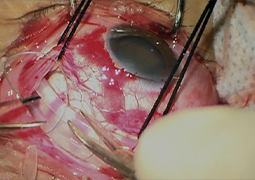

- Presentation of a New Method for Quantitative Determination of Trifocal Intraocular Lens Decentration